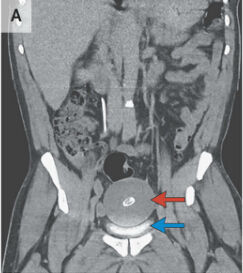

腹腔內游離體的成因目前仍不太清楚,有可能是腸系膜垂下來的脂肪組織壞死後,纖維化鈣化而成,進而在腸道越滾越大、越滾越多。

腹腔內游離體腹腔內游離體是可能因發炎等原因,造成腹腔血液供應不順,腸外脂肪組織壞死,纖維化、鈣化形成白色、外表光滑的物質,游離在腹腔內,由於多數人終身都不會發現,很...